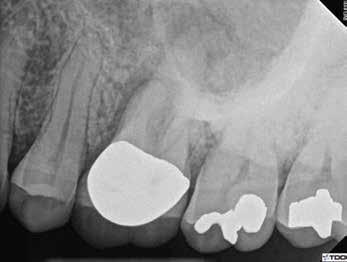

1. a–g. ábrák: A direkt pulpasapkázás lépései. Kiindulási bitewing-felvétel: A meglévő restaurátum közel helyezkedett el a pulpakamrához (a). Kiindulási periapicalis felvétel: Nincs periapicalis elváltozás fennállására utaló jel (b). A pulpaexpozíció (c). A vérzéscsillapítás céljából 20 másodpercen keresztül steril vattagombóccal történő kompressziót követően látható pulpaseb (d). A pulpasapkázás céljából behelyezett anyag, a széli részek tisztázása előtt készült felvétel (e). A röntgenárnyékot nem adó ideiglenes tömés behelyezése után készült felvétel (f). Az első ülés végén a röntgenárnyékot nem adó ideiglenes töméssel ellátott fogról készített röntgenfelvétel (g).

2. ábra: A hat hónapos kontroll alkalmával készített röntgenfelvételen vastag dentinhíd látható a pulpasapkázó anyag alatt.

3. ábra: A hároméves kontroll alkalmával készített röntgenfelvételen megfigyelhető a restaurátum pontos illeszkedése.

A diagnózisunk reverzibilis pulpitis volt. Periapicalis elváltozás jelenlétét nem vélelmeztük. A fogban lévő amalgámtömés eltávolítása során körülbelül egy 3 mm átmérőjű pulpaseb keletkezett a buccalis pulpaszarvnak megfelelően (1. a–g. ábrák) Mivel nem tapasztaltunk jelentős vérzést, és a diagnózisunk reverzibils pulpitis volt, ezért a direkt pulpasapkázás elvégzése mellett döntöttünk.

A kezelést követően a beteg tünetmentes volt. A kérdéses fog a kontrollvizsgálatok során végzett szenzibilitástesztekre fiziológiás reakciókat adott. A hat hónapos kontroll alkalmával készített röntgenfelvételen a sérülésnek megfelelően széles dentinhidat észleltünk (2. ábra). A restaurátum a hároméves kontroll során is megfelelőnek bizonyult (3. ábra)